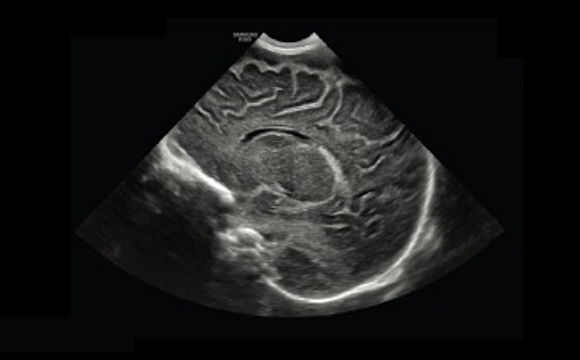

ShadowHDR™ applica selettivamente ultrasuoni ad alta o bassa frequenza per identificare le zone in ombra, come la testa o la colonna vertebrale del feto, dove si verifica l'attenuazione e le compensa permettendo una maggiore visibilità del tessuto.

Colonna verterbrale a